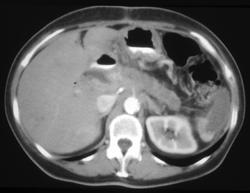

Cirrhosis With Portal Hypertension and Splenic Infarction